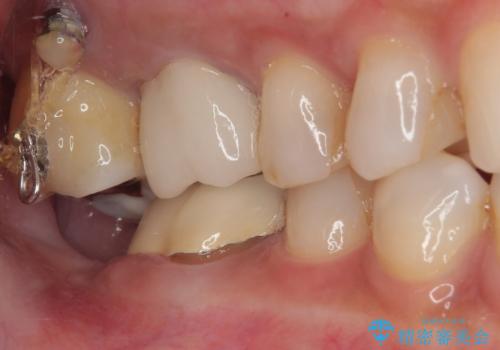

放置した奥歯 部分矯正を併用したインプラント補綴治療

- 右下欠損部のインプラント治療を希望して来院された患者様です。

右下の欠損部を長期間欠損を放置していたことで、咬み合う上の奥歯が動いてしまっていたので、まずは上顎奥歯の部分矯正を行うこととしました。

理想的な咬み合わせに改善した上で、インプラント補綴治療を行うこととしました。